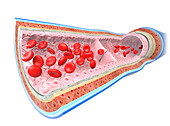

13435209 - Artery and vein, illustration

13435208 - Artery and vein, illustration

13435190 - Artery, illustration

13435191 - Artery, illustration